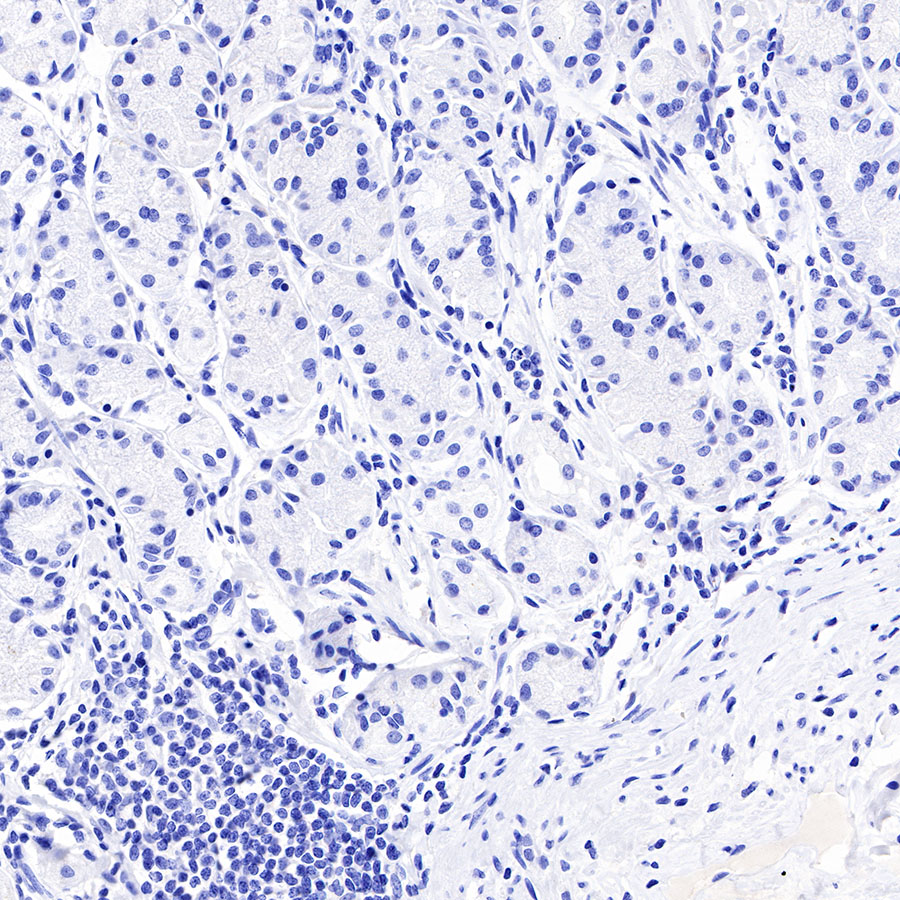

Negative control: IHC shows negative staining in paraffin-embedded human testis. Anti-PAPP-A antibody was used at 1/1000 dilution, followed by a HRP Polymer for Mouse & Rabbit IgG (ready to use). Counterstained with hematoxylin. Heat mediated antigen retrieval with Tris/EDTA buffer pH9.0 was performed before commencing with IHC staining protocol.

Negative control: IHC shows negative staining in paraffin-embedded human stomach. Anti-PAPP-A antibody was used at 1/1000 dilution, followed by a HRP Polymer for Mouse & Rabbit IgG (ready to use). Counterstained with hematoxylin. Heat mediated antigen retrieval with Tris/EDTA buffer pH9.0 was performed before commencing with IHC staining protocol.

Negative control: IHC shows negative staining in paraffin-embedded human colon cancer. Anti-PAPP-A antibody was used at 1/1000 dilution, followed by a HRP Polymer for Mouse & Rabbit IgG (ready to use). Counterstained with hematoxylin. Heat mediated antigen retrieval with Tris/EDTA buffer pH9.0 was performed before commencing with IHC staining protocol.

Negative control: IHC shows negative staining in paraffin-embedded human hepatocellular carcinoma. Anti-PAPP-A antibody was used at 1/1000 dilution, followed by a HRP Polymer for Mouse & Rabbit IgG (ready to use). Counterstained with hematoxylin. Heat mediated antigen retrieval with Tris/EDTA buffer pH9.0 was performed before commencing with IHC staining protocol.